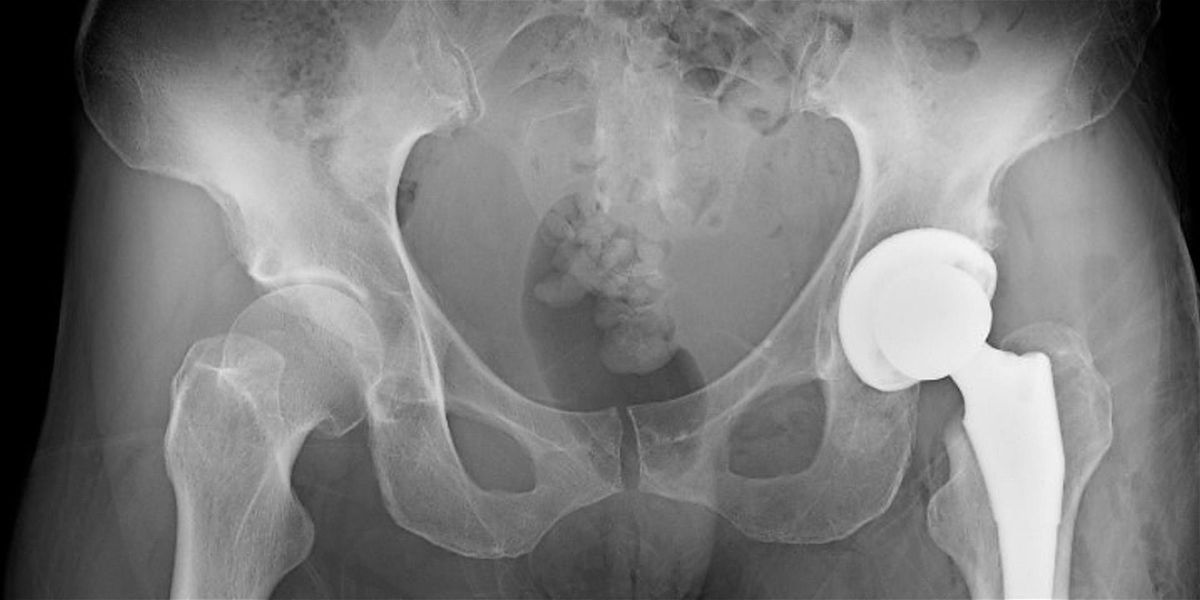

Topic: Total Hip Replacement: Preparation and Return to Dance

Description: Getting a total hip replacement (THR) is a major life decision. Dancers considering and pursuing this procedure often navigate complex emotions as well as logistics. But the recovery process and post-surgery career and life can be rewarding and even transformative.

Physical therapist Dr. Sarah Plumer-Holzman specializes in treating the hip at the Harkness Center for Dance Injuries. In this virtual Saturday Series workshop, she will offer insights on pre-THR considerations and the elements important for success when getting back to dance post-procedure.